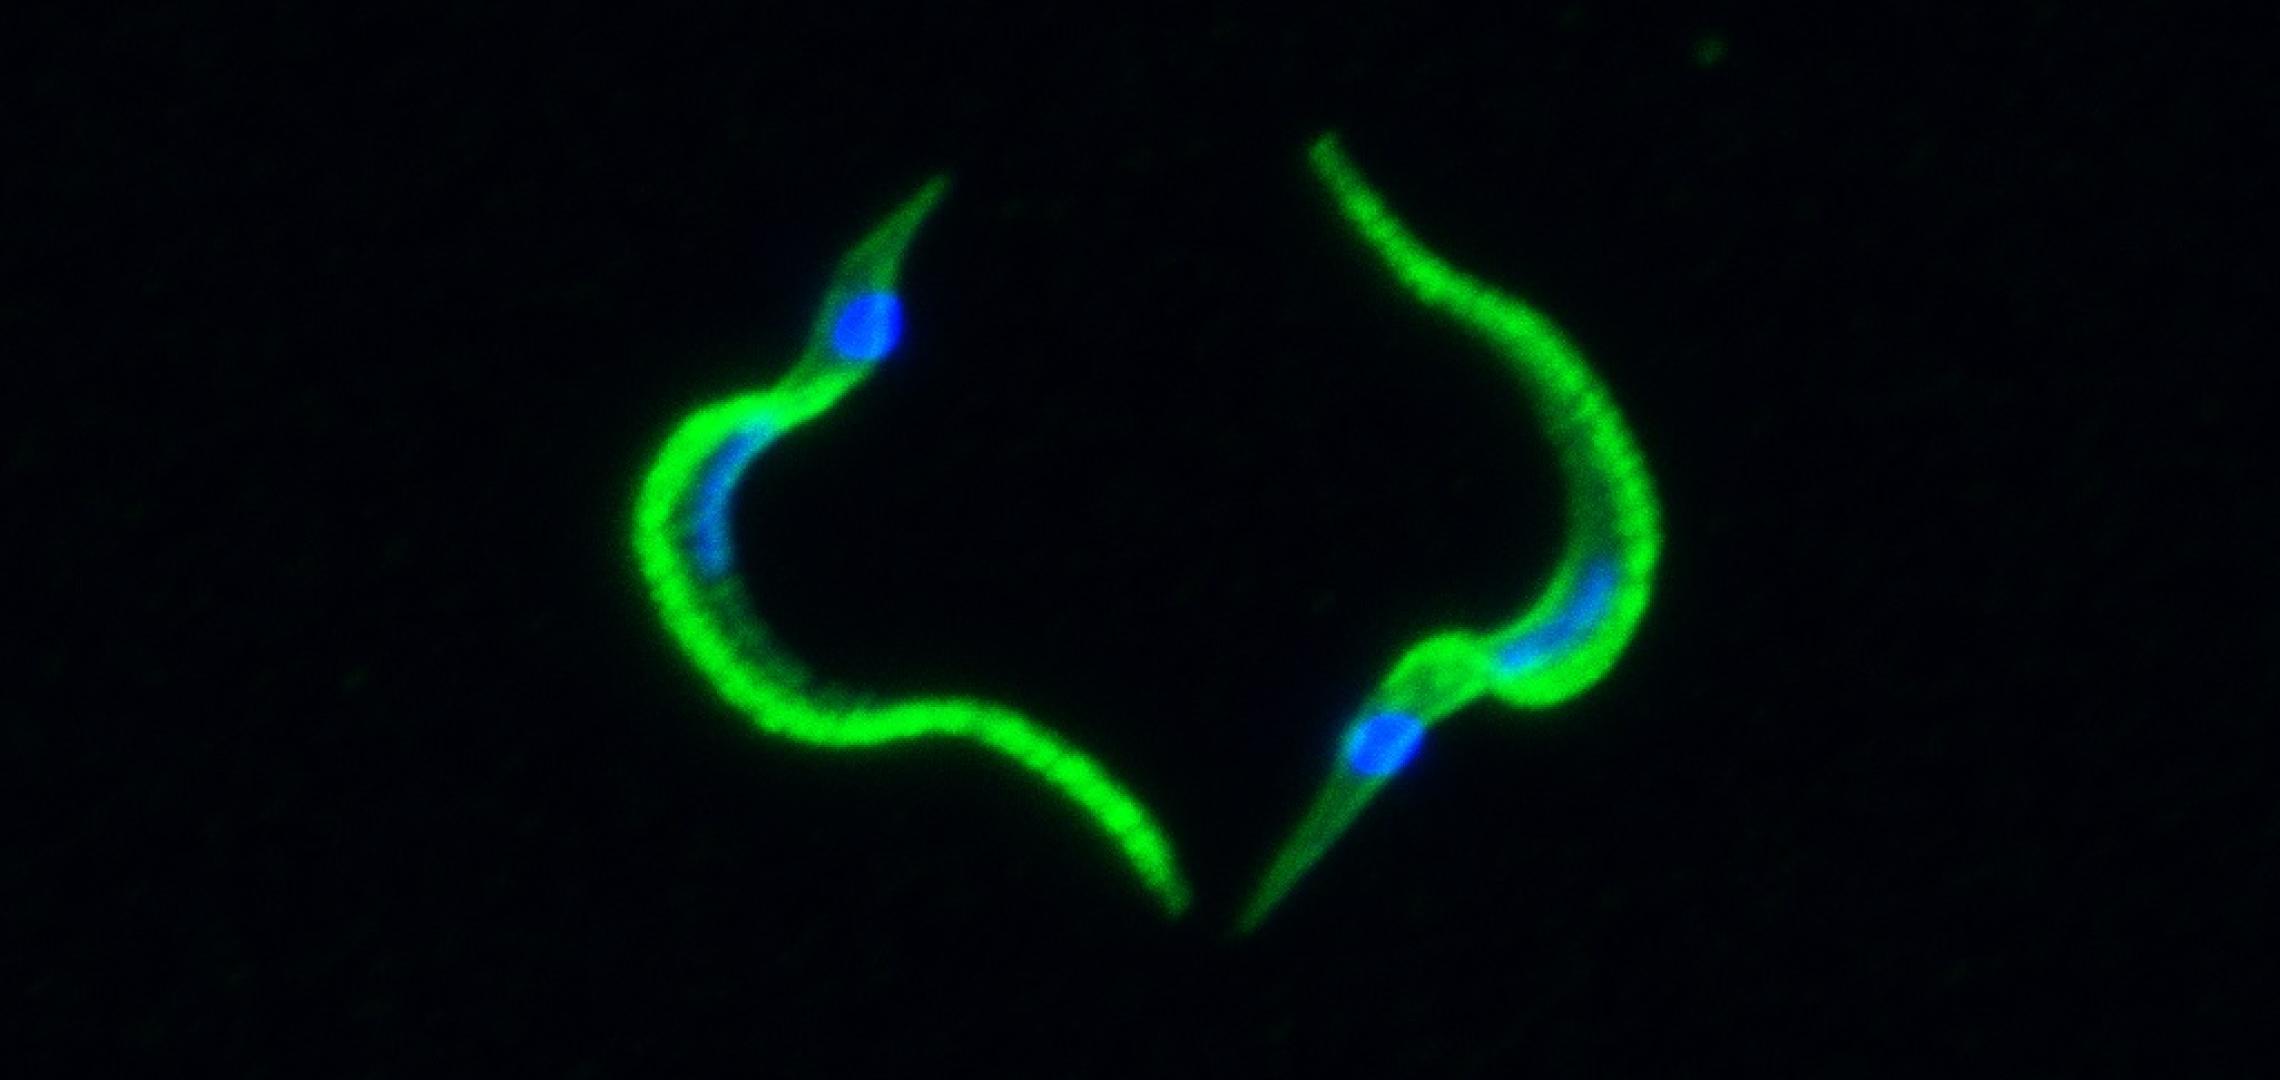

Protozoal infections

Chagas disease, leishmaniasis